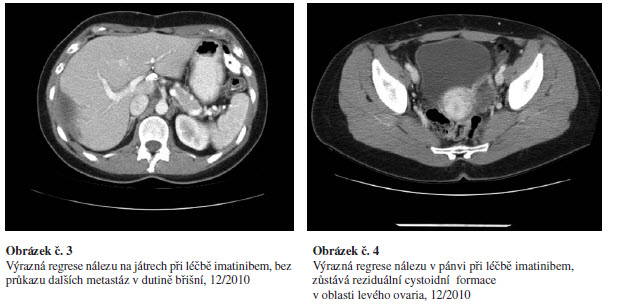

Pacientka je dále pravidelně sledován v tříměsíčních intervalech. Na sérii CT vyšetření (poslední z prosince 2010) dochází k postupné regresi nálezu ad normam, zůstává jen obraz stacionárního cystoidního ložiska jaterního a cystoidně zvětšeného levého ovaria – v.s. nekrotické metastázy, obrázek č. 3,4.

- V lednu 2010 byla pod UZ kontrolou provedena punkce jaterního

cystoidu. Cytologie popisuje oligocelulární materiál s přítomností

lymfocytů a erytrocytů, bez detekce nádorových elementů.